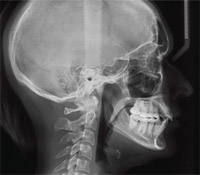

Teleröntgen

A teleröntgen felvétel egy oldalirányú koponyafelvétel. Ez a röntgen kifejezetten fogszabályozási céllal készül, rajta az arcprofil, az alsó és felső fogak egymáshoz való viszonya ábrázolódik, és egyéb a fogszabályozási kezelés megtervezéséhez nélkülözhetetlen mérési eredmények nyerhetők. Mivel a fogak egymásra vetülve ábrázolódnak, ez a felvétel nem alkalmas a fogazat állapotának megítéléséhez.

Rendelőnkben lehetőség van gyermek és felnőtt fogszabályzásra egyaránt, ezért a kezelés megkezdése előtt a röntgenképet számítógépes program segítségével pontosan kiértékeljük, és így a szükséges eljárás, a várható eredmény precízen megtervezhető. Igény szerint a más intézetben történő fogszabályozási kezeléshez a felvételt elkészítjük, és digitális (CD, DVD) formátumban a páciens rendelkezésére bocsátjuk további kiértékelés céljából.